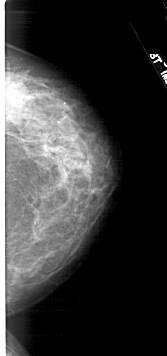

A_1730_1.LEFT_CC

LEFT_CC LINES 5071 PIXELS_PER_LINE 2431 BITS_PER_PIXEL 12 RESOLUTION 43.5 OVERLAY